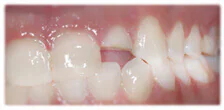

Before